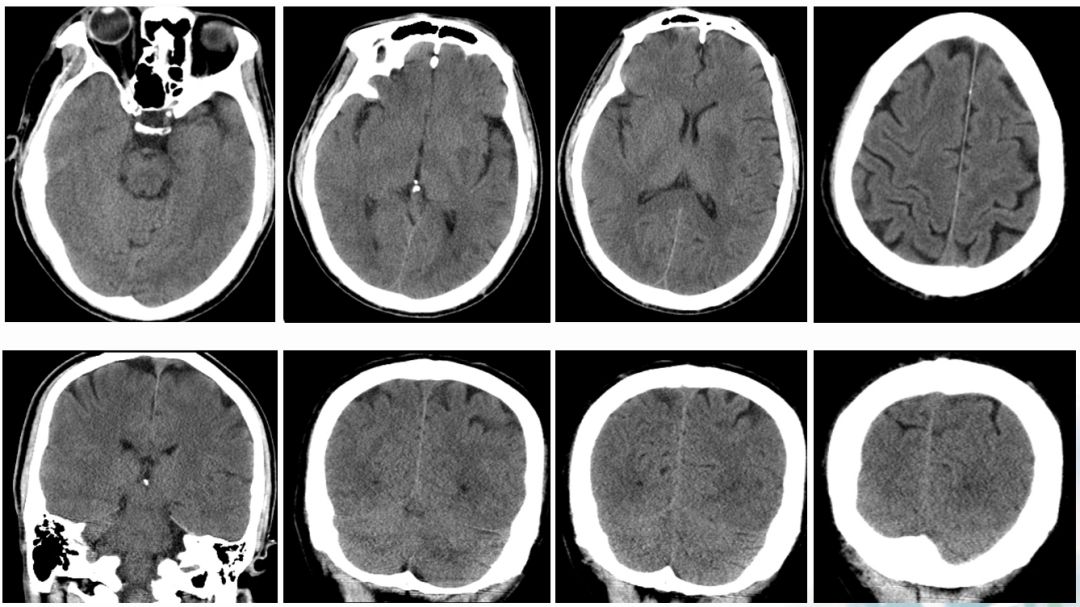

术前CT

ASPECTS评分 8分

术后即刻CT

术后24h CT

术前NIHSS评分16分

术后24hNIHSS评分 2分

术后48hNIHSS评分

术后第3天,患者突然意识丧失,呼叫无反应,刺激右侧肢体无反应,左侧可见回缩,紧急头颅CT提示左侧半球大量脑出血并破入脑室,很快左侧瞳孔散大,深昏迷,家属拒绝行开颅血肿清除术,自动出院。

术后3天CT: